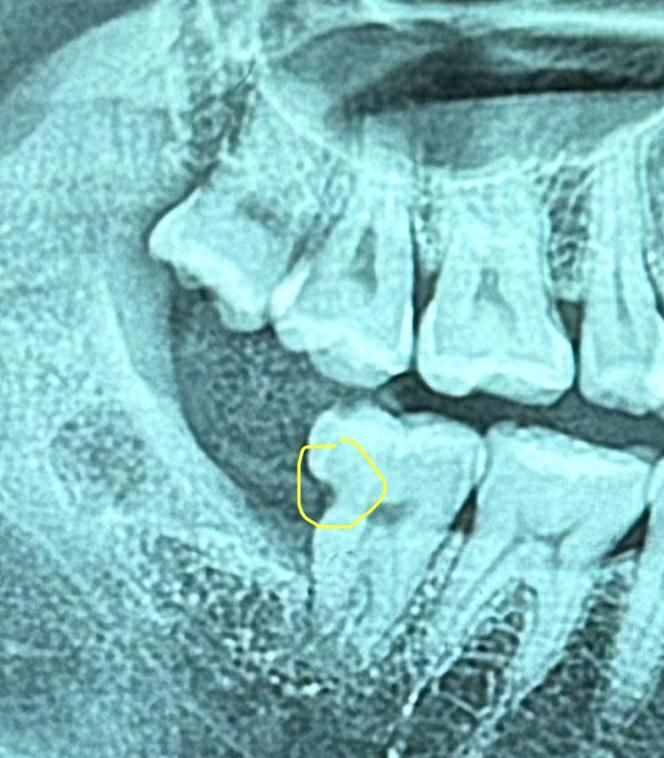

사랑니는 발치한 상태고 옆에 있는 어금니가 사진에 표시된대로 썩은 상태입니다.. 이 정도도 신경치료를 해야하는지 궁금합니다.

• 1번 째 사진

사랑니 때문에 치아 옆면에 충치가 생긴거 같습니다. 불편하지 않으시면 그냥 사용하시고 치료를 하게되면 신경치료 가능성이 높아 보입니다 .옆면은 신경과 가깝습니다.

사진의 선명도가 정확하지 않으나 신경치료보다는 간단하게 치료하는 것으로 가능할 것 같습니다.

사진으로 봤을 경우에는 신경치료의 가능성이 작아 보이기는 합니다.

하지만 충치는 사진보다 더 크게 진행되어 있는 경우가 많기 때문에 충치를 제거해 봐야 알수 있습니다.

옆면 충치의 경우 씹는면보다 신경관과 가깝기 때문에 조금이라도 깊으면 신경치료 가능성은 늘 있습니다. 다만, 지금 엑스레이 사진상 보기에는 신경치료 안하고 한번 떼워볼만합니다.